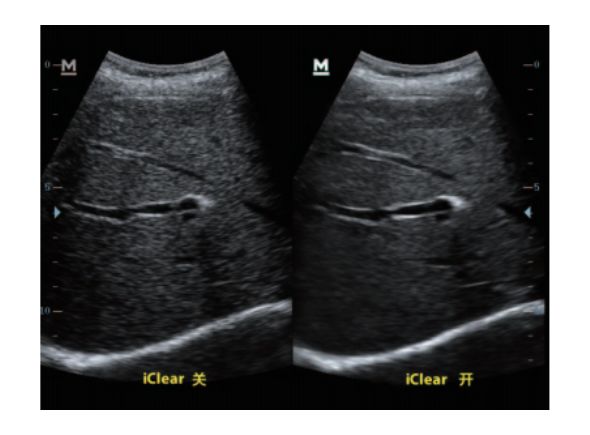

设备型号DP-50 全自动便携式超声诊断系统(迈瑞),该设备为DP 系列超声的较高级版本,具有iTouch 图像一键优化、 iBeam 复合成像、iClear 斑点噪声抑制、宽带频移谐波等技术。

iClear斑点噪声抑制: